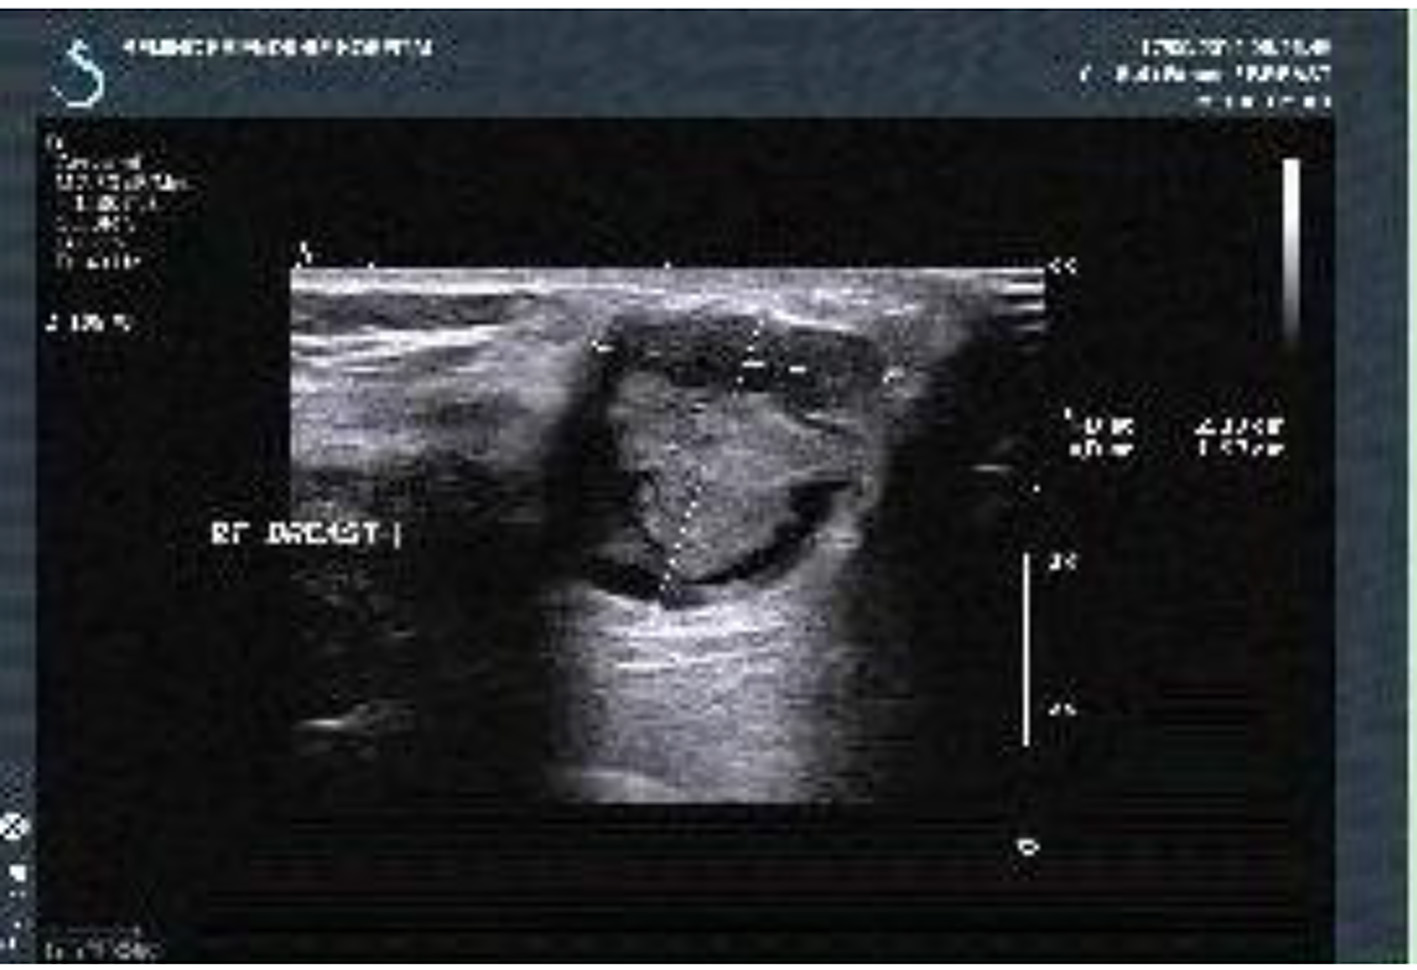

The chemotherapy of TEC (docetaxel + epirubicin + cyclophosphamide) was carried out for two rounds but the tumor did not shrink significantly. After the patient received the treatment of anti-infection and local and debridement, the pus embryo disappeared and no definite pathogenic bacteria were found during the repeated bacterial culture. However, the anabrosis did not shrink. On October 16, 2012, the radical operation of the left breast was performed successfully. On paraffin pathology, a malignant AME was found in the left breast and the tumor had infiltrated into the skin and pectoralis with the distance from the deep resection margin < 0.1 cm. No tumor embolus was seen in the vessel and 1/12 cancer cells of axillary lymph nodes had metastasized. Immunohistochemical examination showed ER (15% weakly +), PR (-), Ki-67 (30-40% +), C-erbB-2 (+), CK5/6 (+), p63 (partially +), CD10 (partially +), calponin (partially +) and CK8 (+). Auxiliary radiotherapy and chemotherapy were carried out. It was found that by the follow-up visit, the intractable subcutaneous hydrops appeared immediately after the operation (Fig. 2). According to the chest CT, bone destruction was seen in the sternum and the left fifth rib (Fig. 3). The patient died from pleural effusion and respiratory failure on August 23, 2014.

Figure 2.

Click for large image

Figure 2. Chest wall Color Doppler ultrasound (on September 6, 2013): multiple flaky echoless region was observed below the incision of the left chest wall with the size of about 3.9 × 0.8 cm.